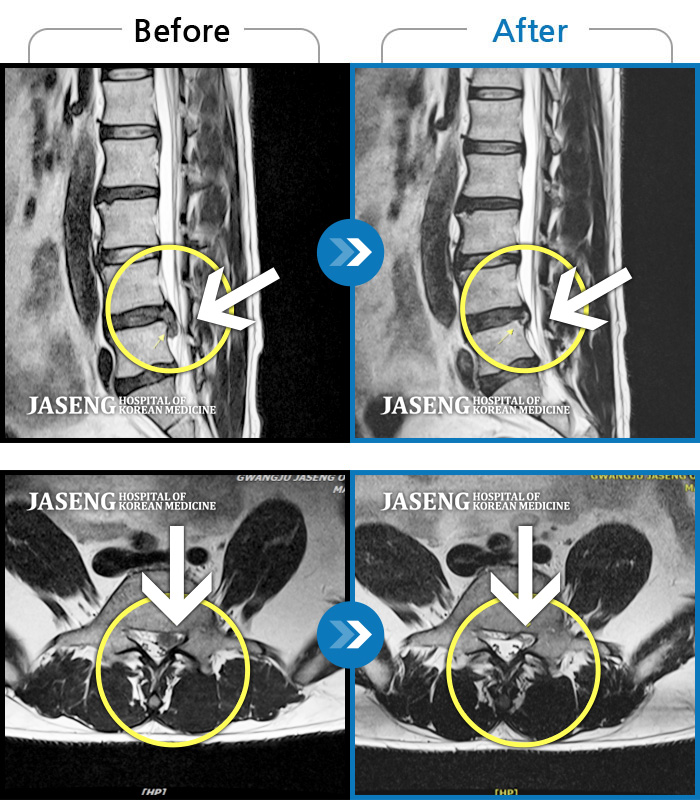

허리디스크

광주 · 김준수 원장

양측 허리 통증, 우측 다리까지 이어지는 통증과 저림, 모든 자세에서 통증 심화

촬영시기

2022.09.02 ~ 2024.08.02

2024.08.14

조회수 124